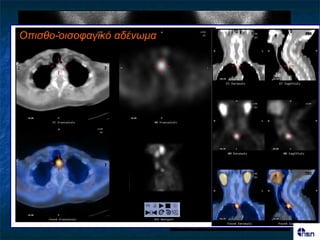

Οπηζζο-ηρατεηαθό αδέλφκα ΓΝΣΟΠΙ΢Η Ονζόημπμ Mibi early Mibi late αδέκςμα; Pertechnetate Αθαίνεζε

Οπηζζο-οηζοθαγηθό αδέλφκα Πνώσμε 2 ώνεξ Φοπνόξ ζονεμεηδηθόξ όδμξ Όδμξ Αδέκςμα Tc-99m Αθαίνεζε